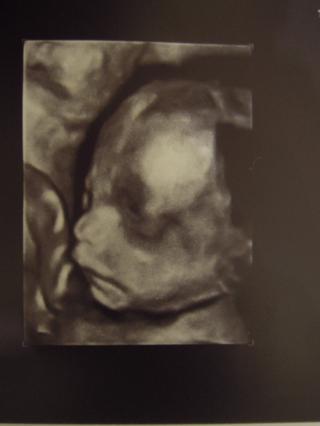

jediny pekny moment dnesneho dna bol ultrazvuk nasej malej karkulky, vsetko je v poriadku, vaha 550g, co mi prislo nejako malo na 24tt, ale vraj je vsetko tabulkove tak si nerobim starosti.. a konecne dam aj ja fotku, vacsinou mame len videjka..

@takitak krasna fotecka mna caka 4d ultrazvuk 5.1. tak sa velmi tesim 🙂 🙂 🙂